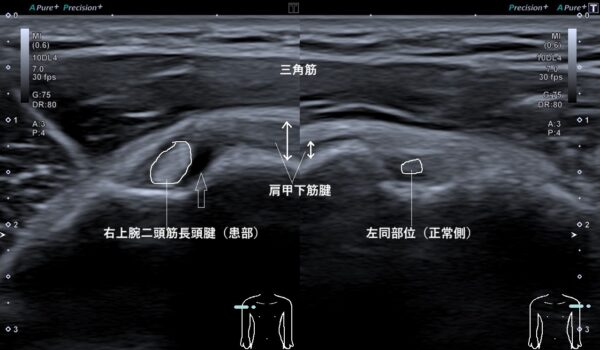

超音波(エコー)画像観察を行うと上腕二頭筋長頭腱が腫れて(画像、白丸の囲みの比較)、その周囲には組織液(潤滑剤のような役目をする滑液)が過剰にたまっていました(画像、上矢印の先の黒い箇所)。

さらに、よく診てみると肩甲下筋腱も過度に引き伸ばされて腫れていました(画像、両矢印の長さの比較)。